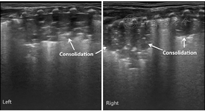

本组MAS患儿的肺脏超声主要表现(表1):(1)肺实变伴支气管充气征:见于所有患儿,重度患儿通常为范围较大、且边界不规则(锯齿状边缘)的实变区(图2,图3,图4);而轻度患儿则以小范围的局限性实变为主要表现(图5);但双侧肺脏实变范围的大小可以不同,而且同一侧肺脏野可以存在大小不同的实变区(图4,图5,图6)。(2)胸膜线异常与A-线消失,见于所有患儿,胸膜线异常表现为病变区胸膜线消失或增粗模糊(图2,图3,图4,图5,图6)。(3)肺不张,是严重肺实变的表现,见于重度患儿,本组12例(17.9%)(图7),严重大面积肺不张时可在实时超声下见到肺搏动和动态支气管充气征。(4)胸腔积液,见于9例(13.4%)患儿(图7)。(5)B-线或AIS,在实变区以外肺野则以AIS或B-线为主要表现。

MAS具有典型的肺脏超声影像学改变。主要特征如下:(1)肺实变伴支气管充气征,见于所有患儿。通常重度患儿实变范围较大、边界不规则呈锯齿状,支气管充气征也较为明显;而轻度MAS则为较小范围的局灶型实变。(2)双侧肺脏或同一侧肺脏不同肺野病变性质与程度的不一致性,双侧肺脏可有范围不同的实变区,同一侧肺脏不同肺野也可以存在大小不同的实变区。(3)肺不张,见于少数重症患儿,更为严重者在实时超声下可见肺搏动或动态支气管充气征。(4)胸膜线异常,表现为病变区胸膜线消失或增粗、模糊。(5)A-线消失,所有患儿在实变区和非实变区均不见A-线。(6)B-线或AIS,非实变区肺组织在超声下常表现为B-线或AIS。(7)胸腔积液,轻度或重度MAS患儿均可有胸腔积液,本组见于13.4%的患儿。但上述超声表现也可见于RDS、肺不张和TTPN等肺病,虽均非MAS的特有改变,但均有各自的特点,超声很容易对它们做出诊断和鉴别诊断[4,5,6,7]。但在肺炎、尤其重度肺炎时,肺脏超声也表现为边界不规则的大面积肺实变[7,15],如无一定经验,仅靠超声表现有时难以将二者准确区别。因此,在借助超声诊断MAS与重症感染性肺炎时,往往需要结合病史。